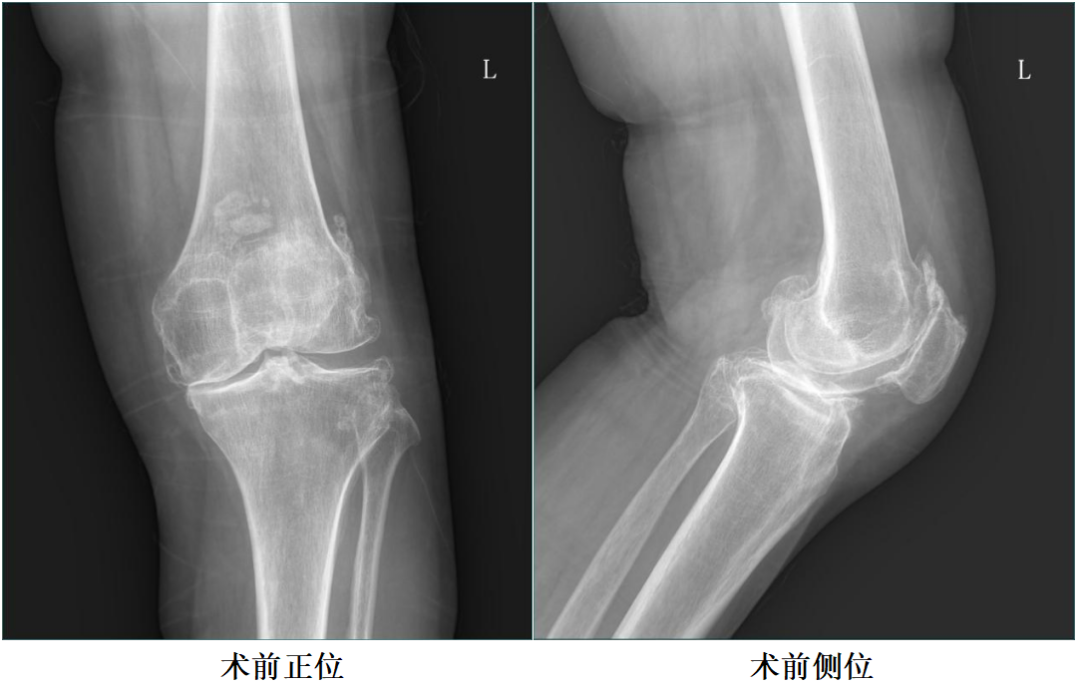

X-Ray:内侧间隙狭窄,站立位内侧间隙消失,外侧间隙正常,膝关节稳定。

诊断:膝关节内侧间室OA。

二、术前X片